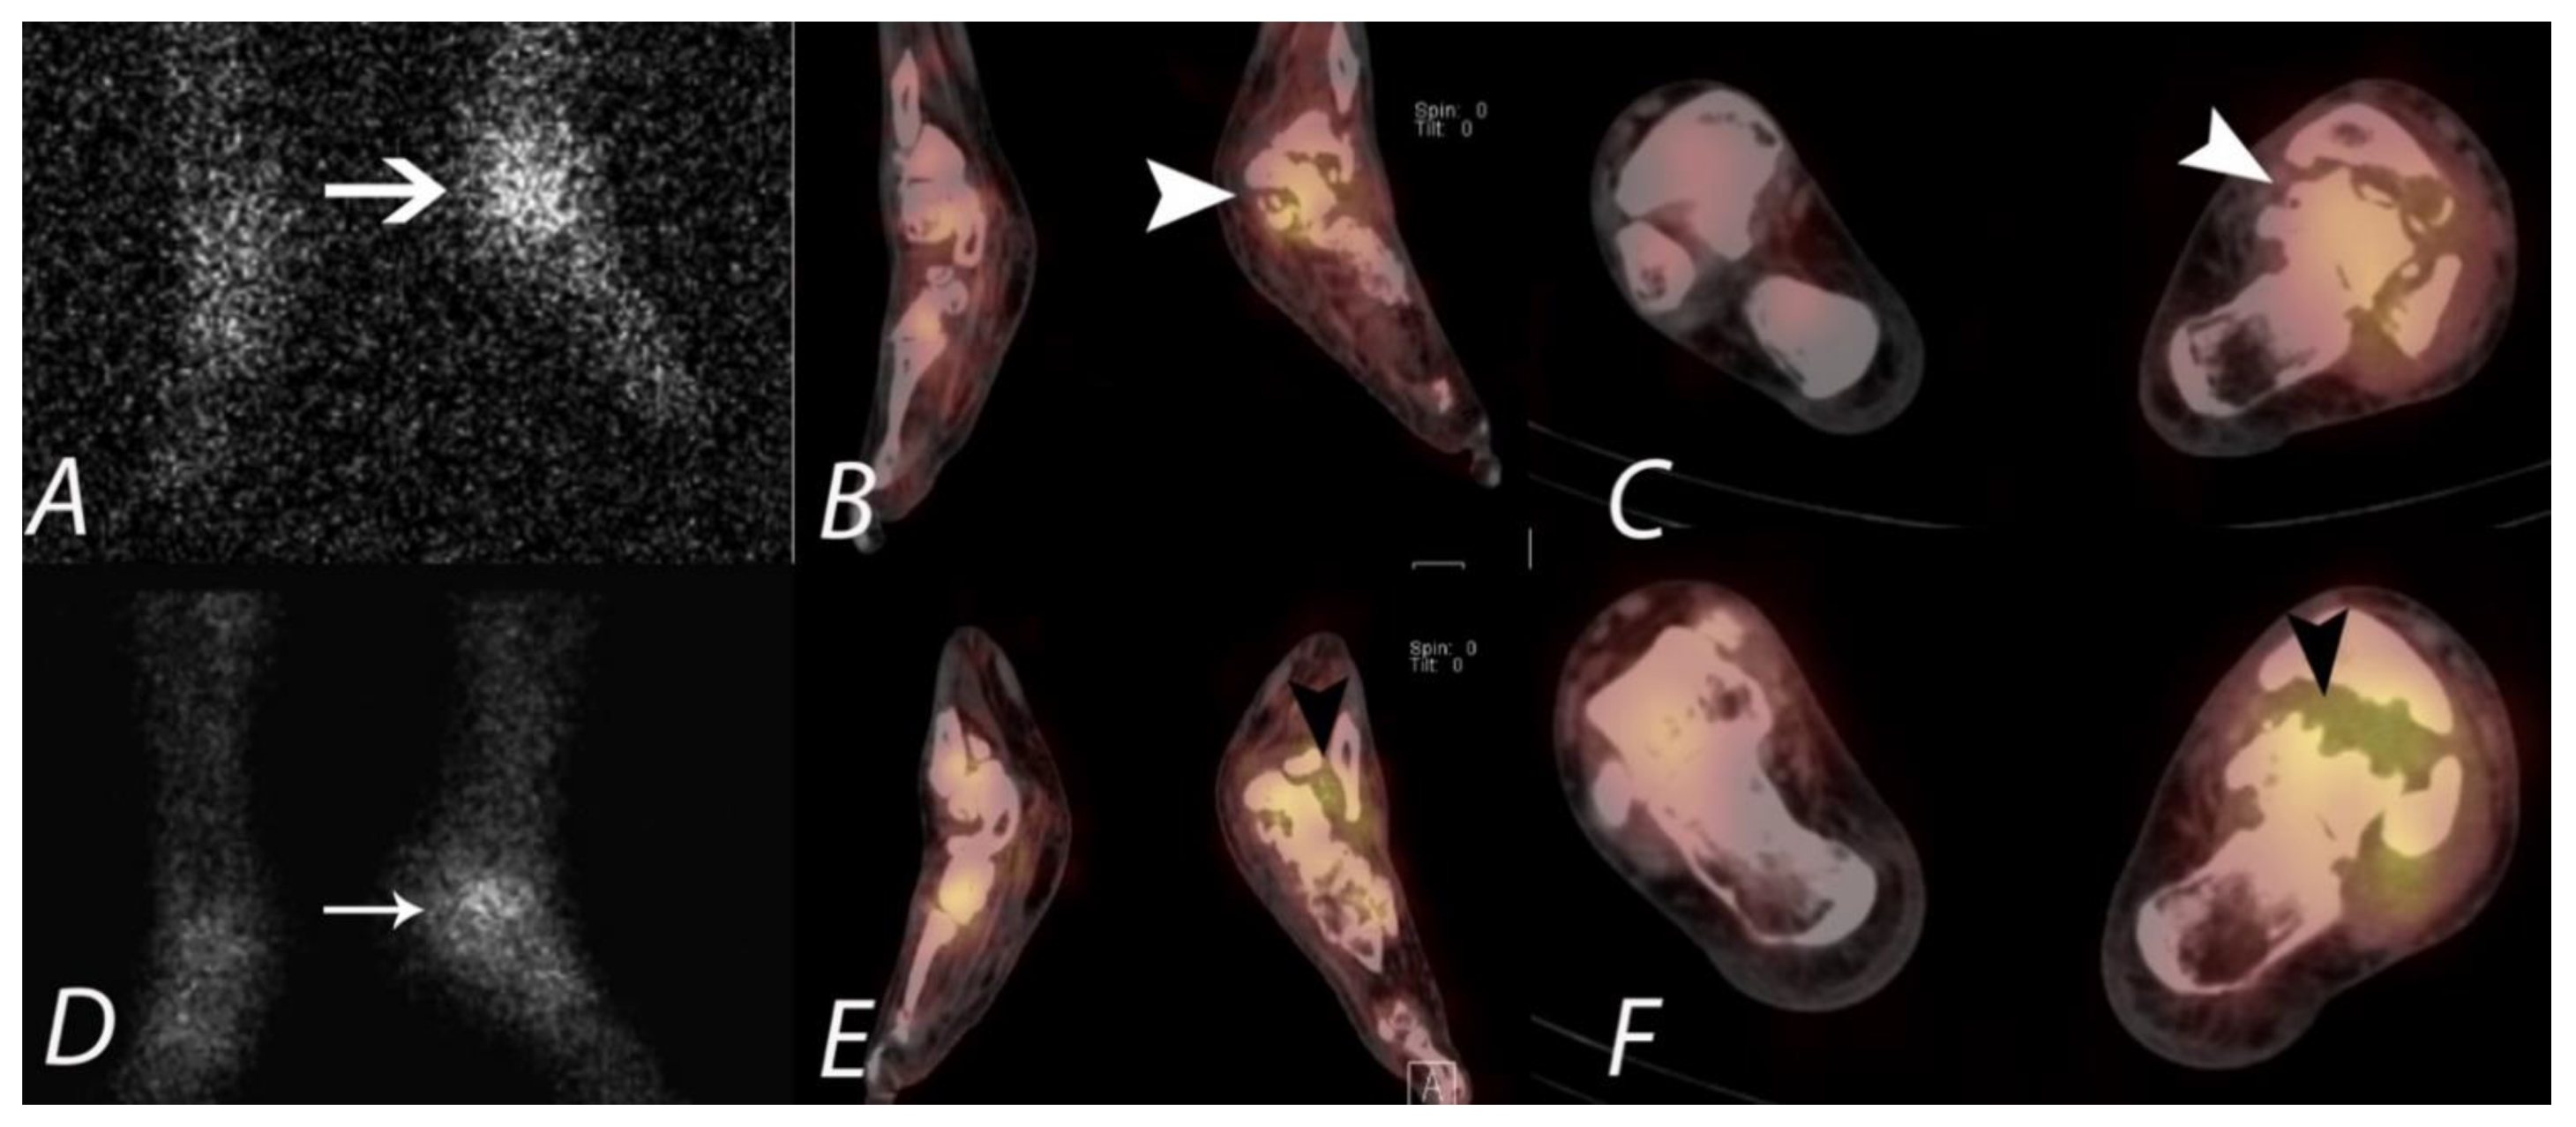

Figure 11.

A young patient presenting with chronic left foot pain underwent three phase bone scan with SPECT/CT. Radiographs were interpreted as normal (not shown). Blood flow and pool images (A,B) demonstrate increased blood flow and pool activity with focal accumulation of activity on the delayed images (C) along the lateral aspect of the mid foot (black arrows). Axial CT image (D) and fused axial (E) and fused coronal (F) SPECT/CT images localize the activity to a well-defined lytic lesion with (white arrowheads) well defined sclerotic rim and a nidus involving the cuboid bone and was interpreted as a possible osteoid osteoma. Patient underwent biopsy, which revealed the lesion to be a benign cartilaginous neoplasm.